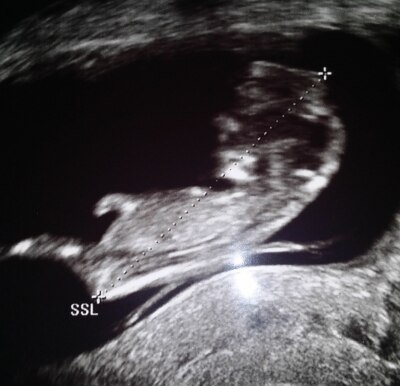

Halli hallo an alle, Ich bin gerade in der 12.ssw (11+3) und das ist meine 2.SS. ich war am freitag in der Untersuchung und da war lait FA alles ok. Jedoch hab ich so ein murmeliges Gefühl aufgrund des Ultraschallbildes, da sich über dem Kopf meines Zwerges etwas seltsames befindet. Oder es scheint mir so zu gehen. Ich würde mich freuen, wenn mir jmd erklären könnte was das ist.

Ich würde sagen, das kann alles mögliche sein. ZB vom Dottersack oder von der Plazenta oder Gebärmutterstrucktur... aber ich glaube nicht, dass es an dem Kopf deines Babys angewachsen ist :-) Ich finde aber, dass die Scheitel-Steiß-Länge dann zu weit nach oben geht. Für mein Verständis hört der Kopf des Babys weiter unten auf und sieht ganz normal aus.

Vielleicht ist es die Hand? Unser Kleiner lag oft mit der Hand auf dem Kopf im Bauch. Ansonsten seh ich es auch so: deine Ärztin hat schon mehr Ultraschallbilder gesehen als wir und wenn die sagt, es passt alles, würde ich das eher glauben als irgendwas, was Laien hier vermuten...!

Also ich kann dich verstehen, spontan fand ich es auch etwas merkwürdig. Finde auch die Messung komisch. Für mich hört der Kopf auch vorher auf.... Wenn es dich arg verunsichert würde ich einfach nochmal beim Arzt anrufen, vielleicht gibt es eine ganz einfache bzw. harmlose Erklärung dafür. US Bilder können oftmals verwirren....

Nein,der Kopf hört nicht schon vorher auf,ja,der Teil gehört noch zum Kopf und ja,das sieht normal aus... Ist einfach eine bescheidene 2D-Aufnahme ;) In dem Schwangerschaftsalter ist der Kopf übrigens noch so riesig,also bleib ruhig,dein Baby ist vollkommen normal!

Für mich ist das eindeutig eine hand, vorne sieht man die fingerchen. aber die messung stimmt nicht. Der Kopf hört weiter unten auf, man sieht das ja genau an der rundung.

Ich denke auch das alles normal aussieht und es die Hand deines Babys ist. Wenn man genauer hinsieht, sieht es ein bisschen aus wie ein Hut Alles Gute noch